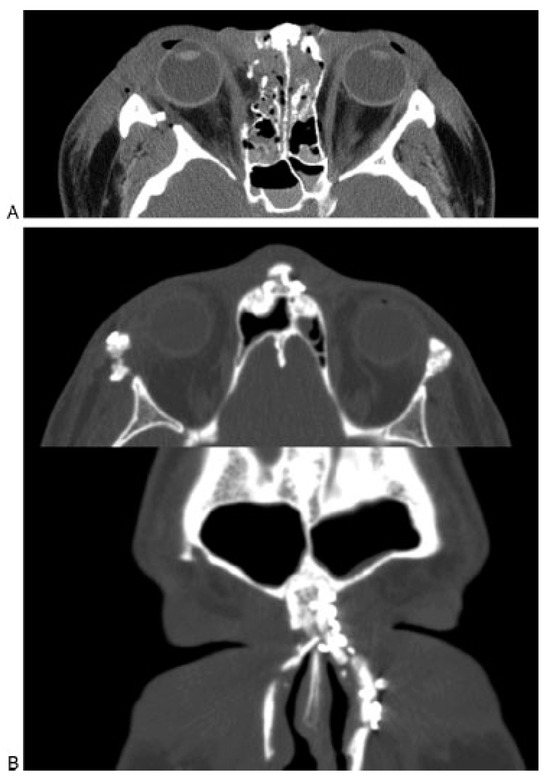

A thin-cut (1.0 to 1.5 mm) axial, coronal, and sagittal computed tomography (CT) scan is the radiological gold standard for diagnosis of frontal sinus fractures. Axial images provide the best information about the anterior and posterior tables (Figure 2); coronal images are used to assess the sinus floor and orbital roof (Figure 3). Sagittal reconstructions can be useful in assessing the patency of the frontal recess (Figure 4), and three-dimensional recon- structions may help to visualize the external contour deformity seen less clearly with two-dimensional cuts alone (Figure 5).

Figure 2.

Axial computed tomography scan demonstrating a frontal sinus fracture involving both the anterior and poster- ior tables. (A) Marked anterior table disruption. The white arrow points out a displaced posterior table bone fragment. (B) Disruption of the nasofrontal recess.